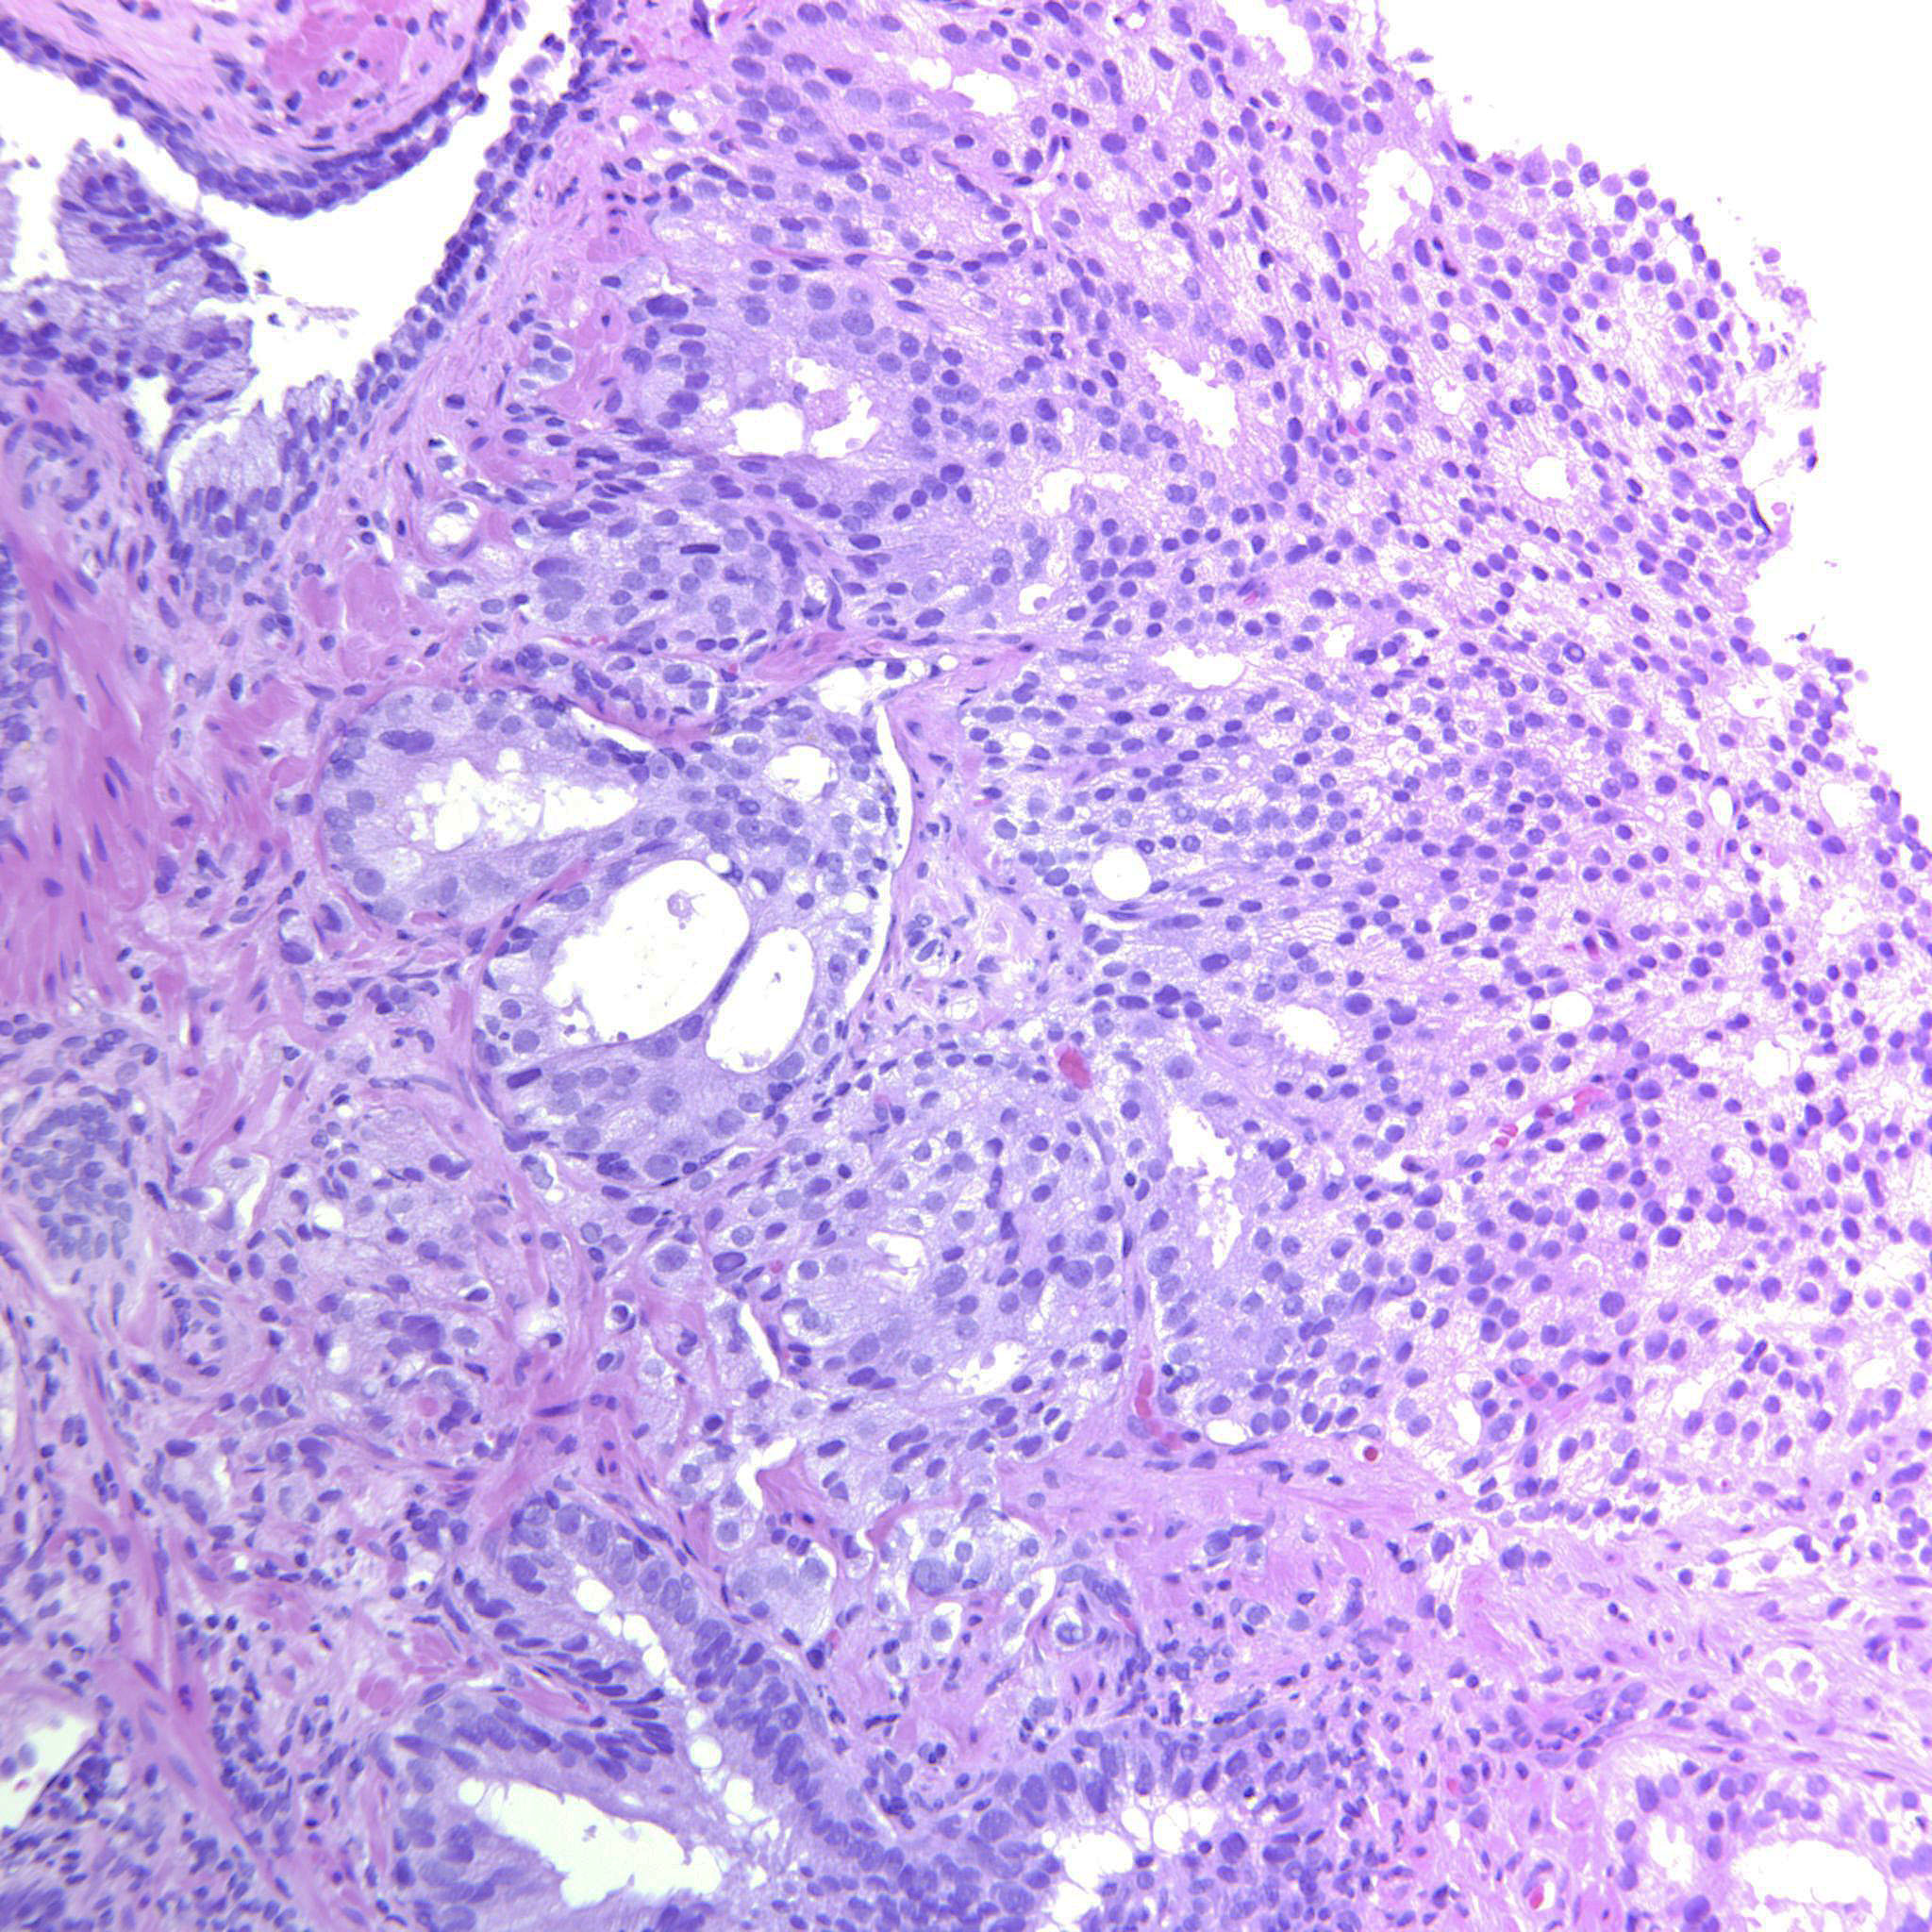

Consensus grade: GS 4+4=8 (ISUP 4)

Case description (by case creator):

Large cribriform sheets and also tightly packed poorly formed glands. Some seem to be solid nests or single cells but not convincing for GP5.